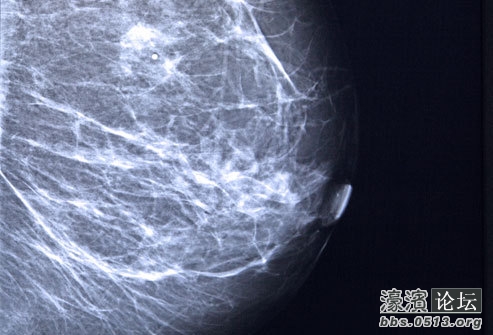

T& ]3 a8 c2 O% | 乳腺癌越早发现越易治疗。乳腺X光片可在尚不被感知时发现肿瘤。美国癌症协会建议女性从40岁起,定期做乳腺X光片,因为此时已是乳腺癌发病高峰期。

J! d: w; U7 ~ 除了乳腺X线摄片,医生还会建议进行乳房超声波检查来排除乳房囊肿的可能性。核磁共振检查也可以帮助可能患有乳腺癌的高风险人群进行更详细的检查。9 W/ X, Q- J# K4 H